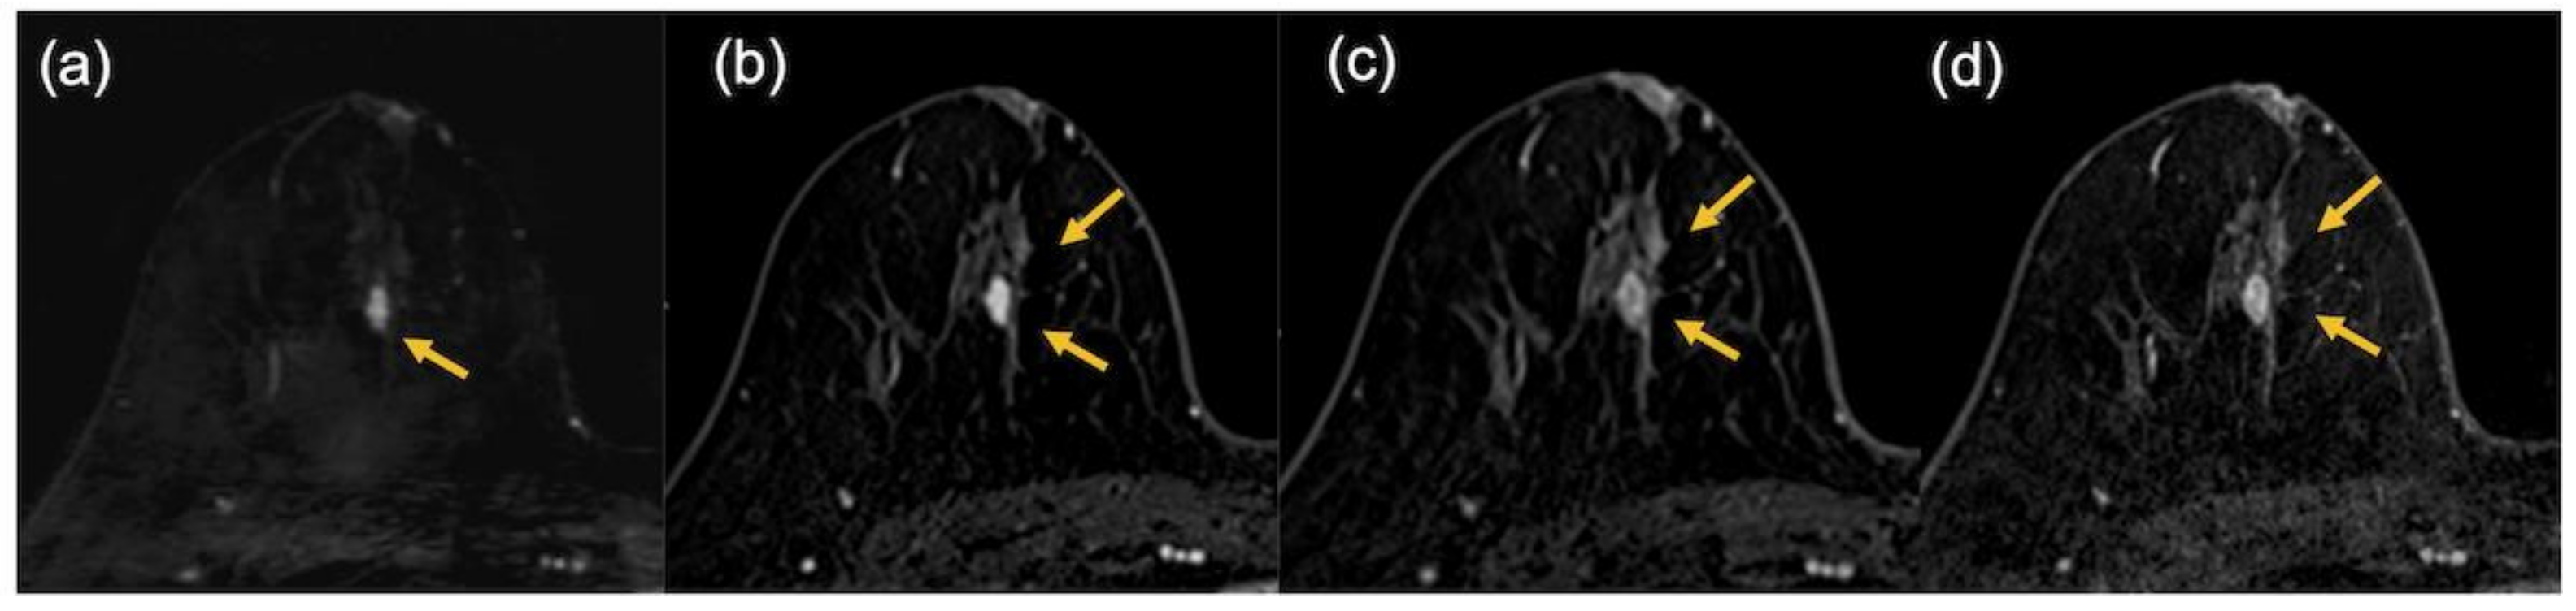

2.2. Image Evaluation